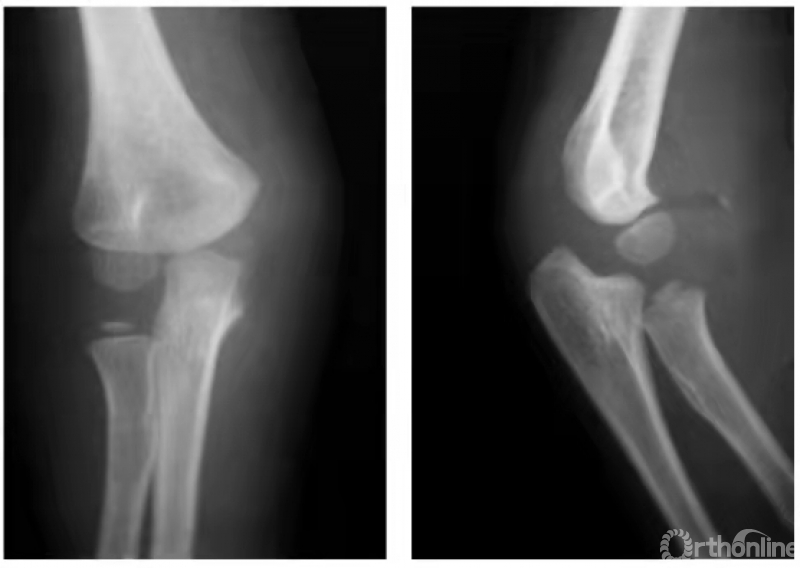

例:6岁男孩右肘伤后(图1),内上髁损伤后肿胀,局部可触到活动的骨块,但X线片未见异常(因该骨骺尚未骨化)。5年后拍片健侧(左侧)内上髁骨骺正常显现,右侧内上髁骨骺呈一三角形骨片并略下移(图2)。

图1

图2